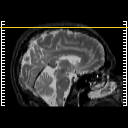

MR Study #6, March 17, 1991 -- Slice #50

[Home][Help][Clinical][Tour 1][Tour 2] Slice 50